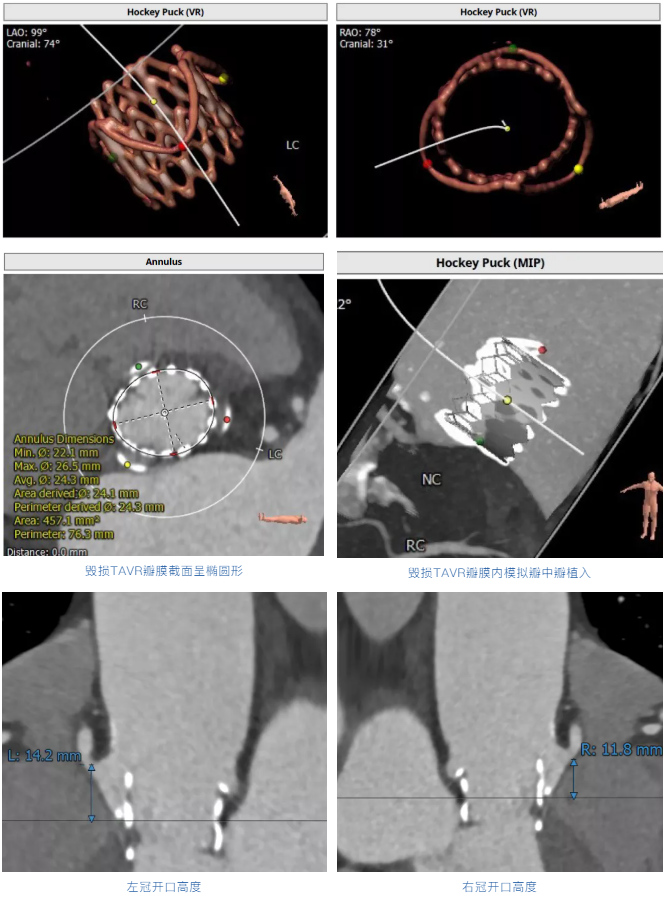

术前经详尽评估患者病情,通过CT重建观察到既往植入的自膨式TAVR瓣膜呈椭圆形,测量瓣环直径,及双侧冠脉开口高度,并评估外周血管入路。由于患者外周血管钙化严重且迂曲,经外周血管途径有较大风险,决定对该病例采用经心尖途径行TAVR瓣膜内 “瓣中瓣”手术。但第二次经心尖途径又将面临心脏、肺、胸壁肌肉组织的粘连,手术难度大。经术前反复讨论和仔细测量毁损TAVR瓣膜的平均内径和冠脉开口高度,决定选用25号 Renato球扩瓣膜。Renato球扩式瓣中瓣可以提供更强的径向支撑力,瓣架高度低,术前模拟植入评估显示冠脉梗阻风险低。手术过程顺利,最终瓣中瓣植入位置理想,功能表现出色,主动脉根部造影及经食道超声观察无瓣中及瓣周反流。